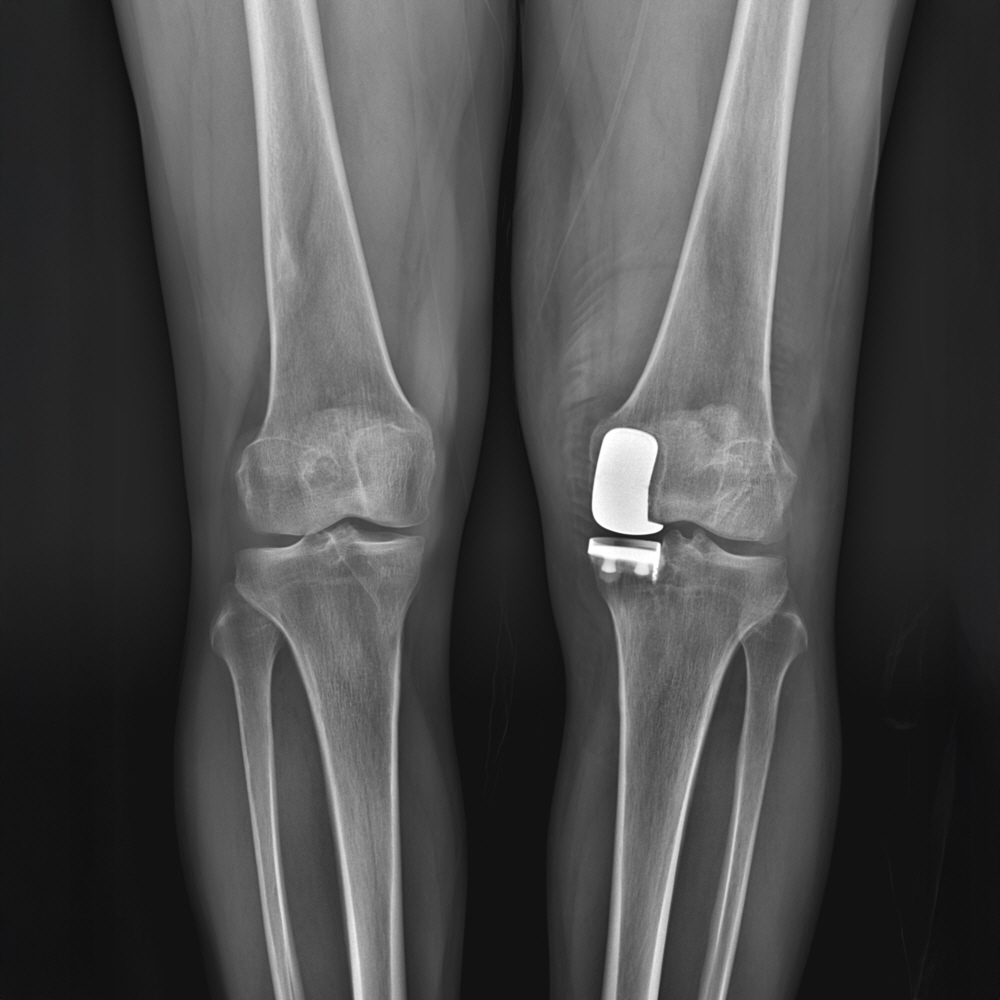

무릎관절 내측면 절반만 관절염이 있을 때, 해당 구획만 인공관절로 바꿔주는 방법입니다. 무릎의 구조상 주로 안쪽 관절면의 퇴행성관절염이 발생하며, 바깥쪽 연골은 상대적으로 잘 유지되는 경우가 많습니다. 이런 상황에서 마모가 진행된 안쪽면 절반만 부분인공관절로 교체하고, 다른 구획의 구조물은 본인의 것을 유지하는 치료법이 ‘무릎 인공관절 반치환술(부분치환술)입니다.

최소피부절개(10cm 이하)로 손상된 무릎관절의 일부를 제거하고, 내측면만 인공관절로 바꿔주는 치료법으로 기존의 전치환술에 비해 회복속도가 빠르며, 수혈이 필요없고, 입원기간이 짧습니다. 관절의 움직임이 자유롭다보니 수술후 무릎을 강제로 꺾는 재활치료가 필요없으며, 다른 구획들의 연골,인대,연골판 등을 손상없이 보존함으로 정상적인 무릎관절로 회복이 가능하며, 일상생활로의 복귀도 빠릅니다.

61세 여성 ㅣ 퇴행성관절염 ㅣ 인공관절부분치환술

증 상

우측 무릎 내측부에 국한된 통증으로 걷거나 계단 오르내릴 때 통증이 심함. 해당부위를 누르면 아프고, 통증이 심할 때는 약물치료, 주사치료를 병행하며 지내옴. 최근들어서는 무릎이 붓고, 통증이 심해지며, 화끈거리는 열감까지 생김. 쭈그려 앉기 힘들고, 양반다리가 안되며 앉았다 일어설 때 통증이 심해짐. 동네의원에서 연골주사, DNA주사, 콜라겐 주사, 스테로이드주사 및 충격파, 도수치료 등을 꾸준히 했으나 증상차도가 없어 내원함.

치료

검사상 내측부에 국한된 퇴행성관절염으로 다른 구획은 연골상태가 양호하여 내측부 인공관절 반치환술(부분치환술)을 시행함.

걷거나 쭈그릴 때 좌측 무릎 내측부에 심한 통증이 발생. 예전에 무릎을 심하게 다친적 있음. 이후로 지속적인 통증으로 인해 꾸준히 치료를 하였으나 증상호전되지 않아 시행한 정밀검사상 연골판 파열을 동반한 내측부 외상성 퇴행성관절염으로 진단받음. 꾸준한 치료에도 차도가 없고, 더 통증이 심해짐. 계단 내려갈 때랑 쭈그려 앉을 때 통증이 심하며, 내측부뿐만 아니라 오금 쪽에도 통증이 심해짐.

정밀검사에서 내측부 외상성 퇴행성 관절염과 연골판 파열이 관찰됨. 십자인대손상은 없었으며, 다른 구획에 관절염 소견도 없어 내측부 인공관절 반치환술(부분 치환술)을 시행함.